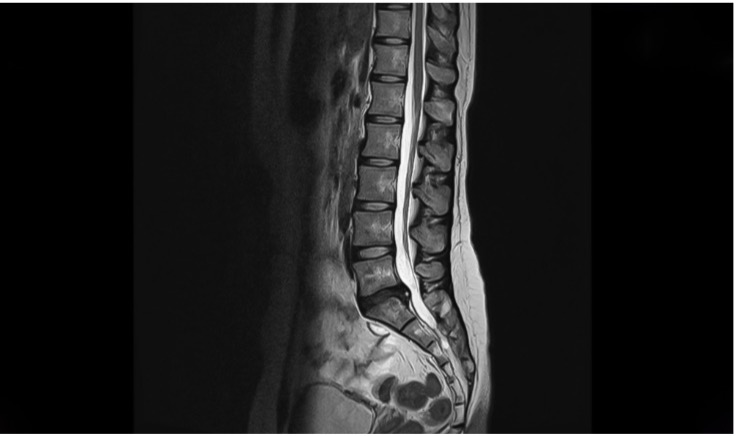

spine-photoEven with this approach, therapists, however qualified, are trained to manually assess conditions but ultimately can only come up with a provisional diagnosis. To confirm this diagnosis, additional scans, such as EMG to look at nerve function, MRI, Xray and ultrasound may be needed. Even then, some conditions are invisible to such scans. Scans may thus be able to eliminate some causes, but not able to confirm the actual cause. A good example is that neither MRI nor X-ray can see muscle spasms, the latter being responsible for a lot of neuropathic problems, such as sciatica.